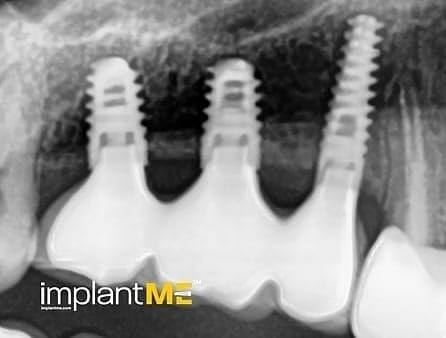

Τα ελκυστικά και ιδιαίτερα υγιή δόντια δεν είναι μόνο καθοριστικό μέρος της εμφάνισής μας, αλλά και της προσωπικότητάς μας. Παλαιότερα, η απώλεια ενός ή περισσοτέρων δοντιών είχε καθοριστικό αντίκτυπο στον τρόπο εμφάνισης των ανθρώπων. Λόγω της σύγχρονης στοματικής εμφυτευματολογίας, αυτό δεν συμβαίνει πλέον. Με συγκριτικά μικρές χειρουργικές επεμβάσεις από το στόμα, μεμονωμένα ή όλα τα ελλείποντα δόντια μπορούν να αντικατασταθούν από εμφυτεύματα, αισθητικά και λειτουργικά ίσα με τα φυσικά δόντια. Μέσω της εισαγωγής εμφυτευμάτων που σχηματίζονται σε ρίζα, είναι δυνατόν να αποφευχθούν αλλοιώσεις των γειτονικών δοντιών και να αγκυρωθούν στεφάνες που δύσκολα διακρίνονται από τα πραγματικά δόντια στα κενά των δοντιών. Οι στεφάνες ή οι γέφυρες που υποστηρίζονται από εμφύτευμα στερεώνονται στα εμφυτεύματα που είναι αγκυροβολημένα στο οστό, γεγονός που δίνει στους ασθενείς μια αίσθηση μάσησης σχεδόν διακριτή από τα δόντια τους. Σε περίπτωση πλήρους έλλειψης δοντιών, τα εμφυτεύματα μπορούν να παρέχουν αξιόπιστες αγκυρώσεις για αφαιρούμενα προσθετικά καθώς και για μεγάλες σταθερές γέφυρες.

Τα οδοντικά προσθετικά που υποστηρίζονται από εμφύτευμα βρίσκονται όσο πιο κοντά μπορείτε να φτάσετε στα φυσικά δόντια. Τα στεφάνια των εμφυτευμάτων βαθμολογούνται με τη φυσική τους εμφάνιση, τα εμφυτεύματα με τη σταθερότητα τους και και τα δύο με τη θετική τους επίδραση στη λειτουργική συντήρηση ολόκληρης της μαστιχικής συσκευής.